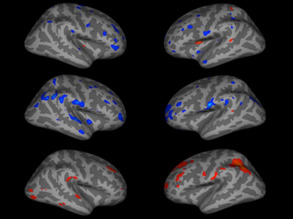

Trouble with Spikes